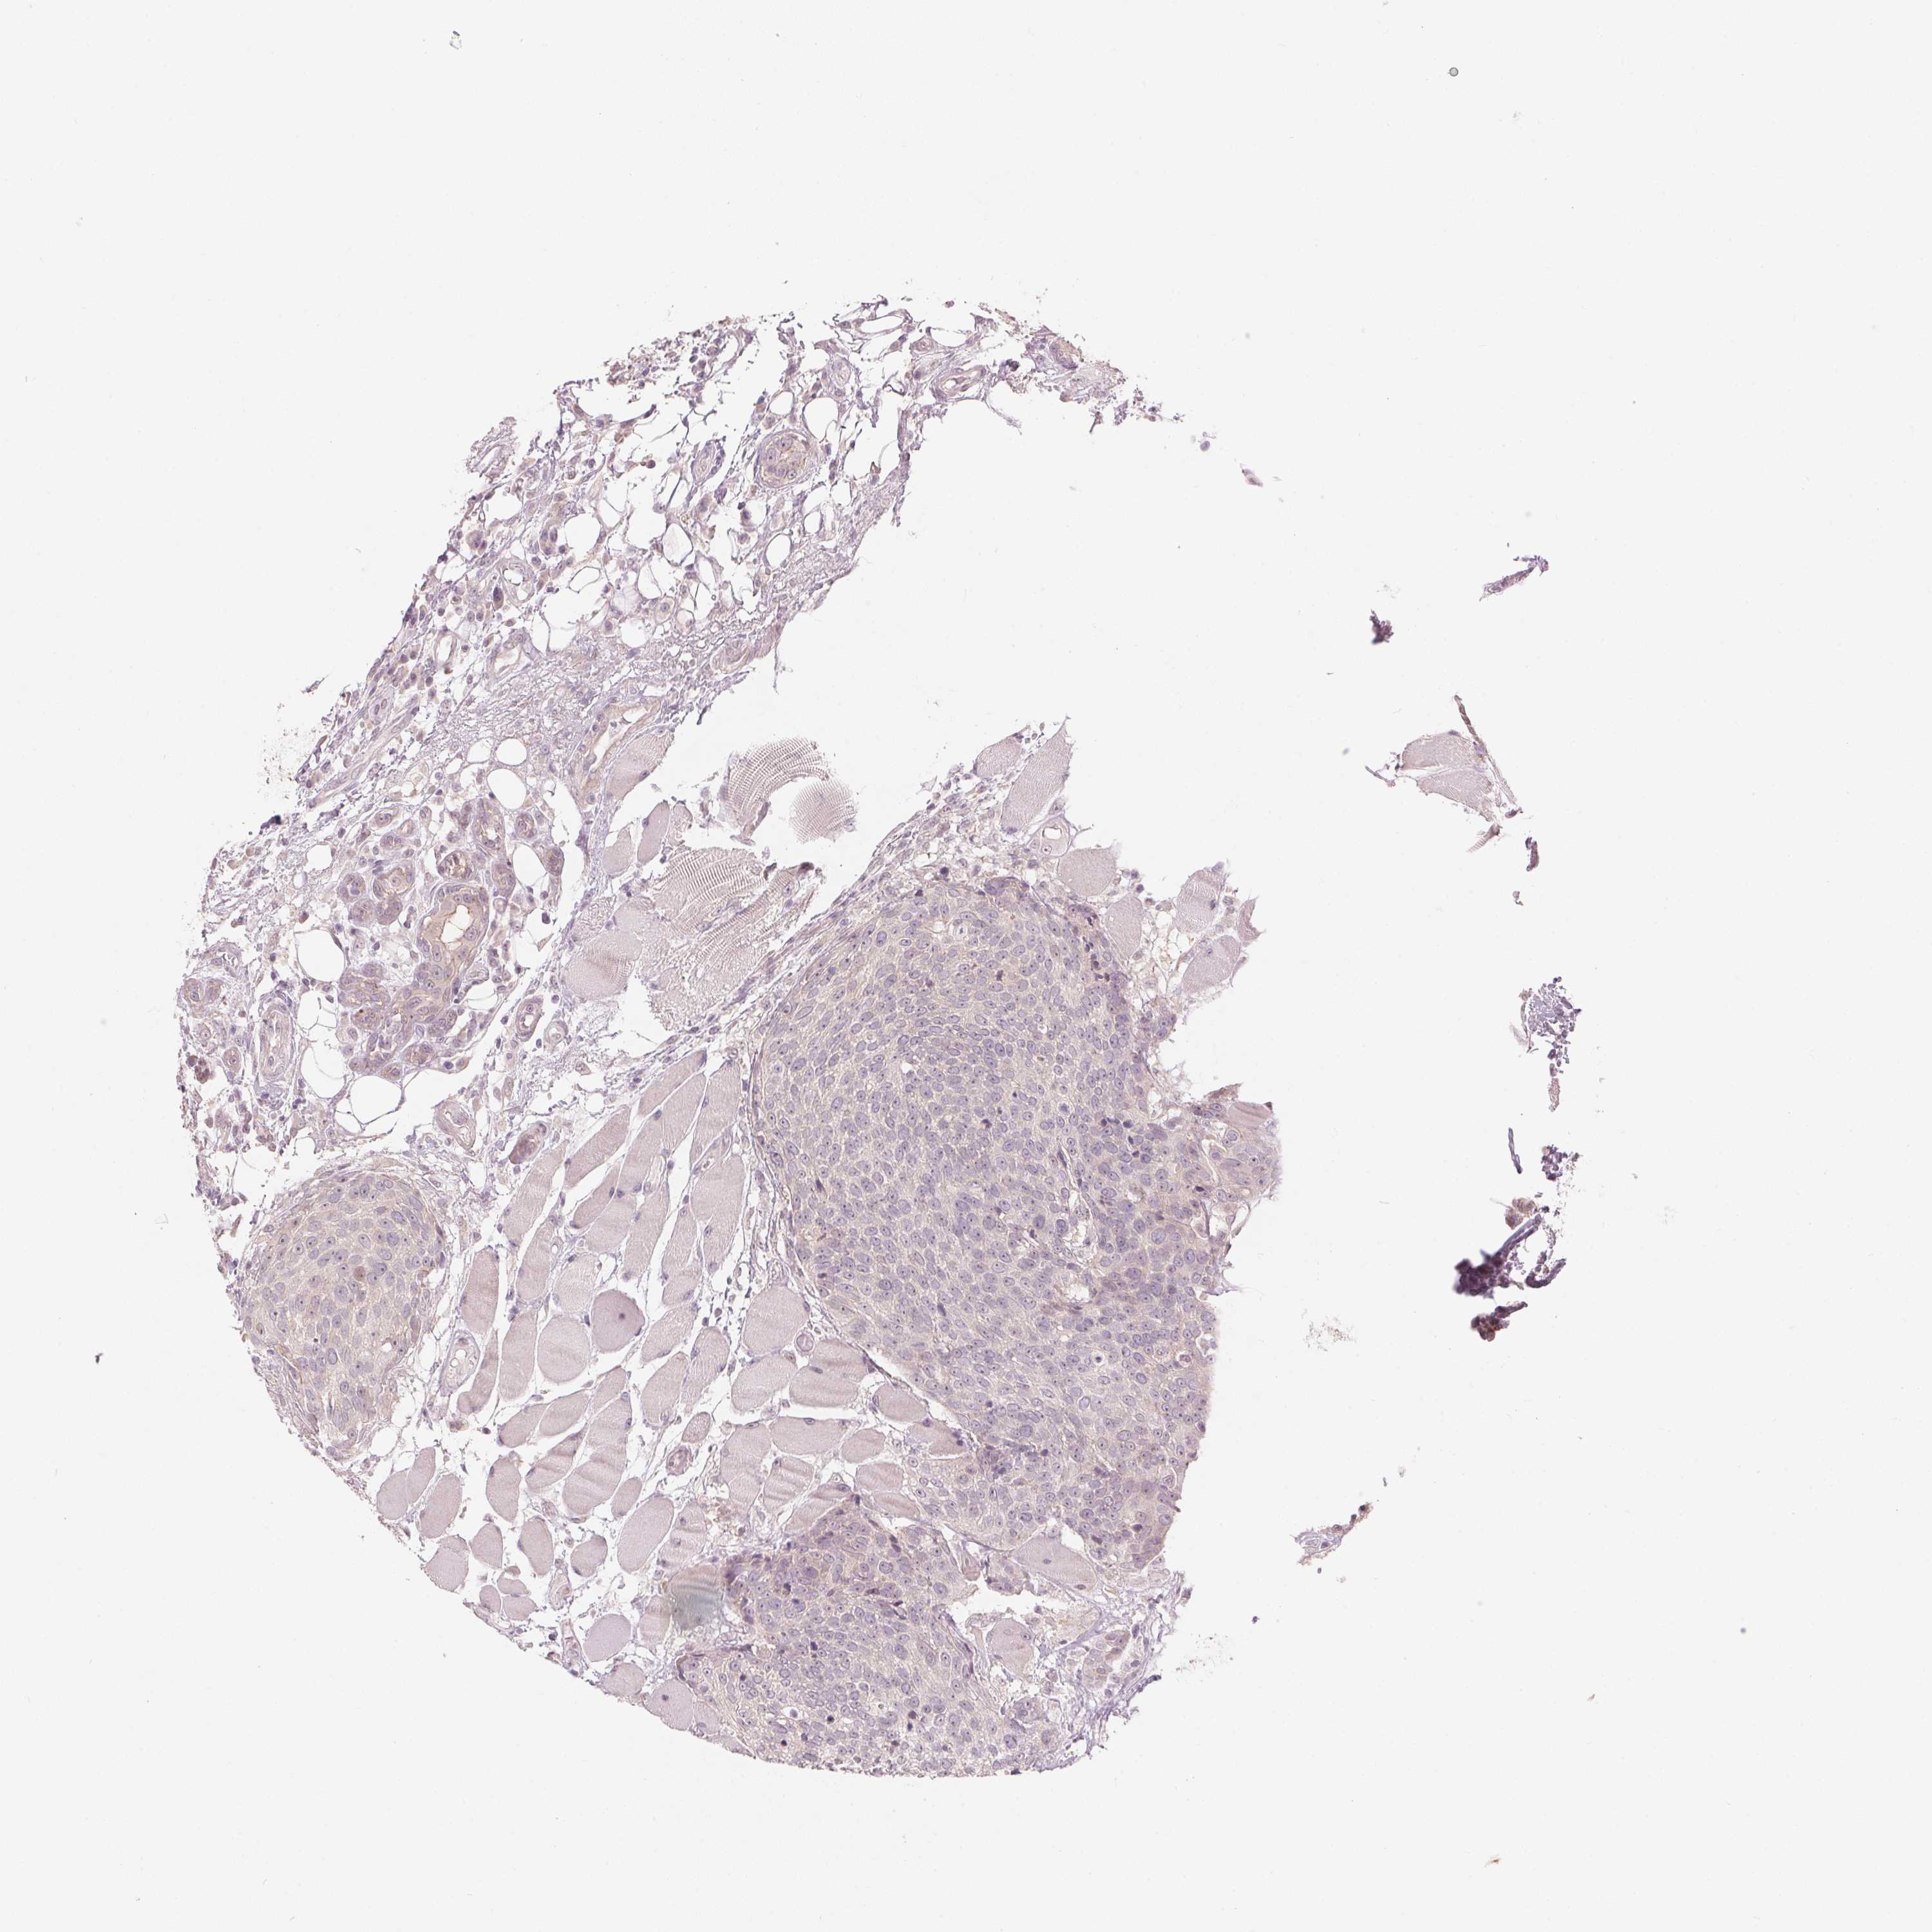

HEAD AND NECK CANCER - Protein expressioni

A mouse-over function shows sample information and annotation data. Click on an image to view it in a full screen mode. Samples can be filtered based on level of antibody staining by selecting one or several of the following categories: high, medium, low and not detected. The assay and annotation is described here.

Antibody stainingi

Antibody staining in the annotated cell types in the current human tissue is reported as not detected, low, medium, or high, based on conventional immunohistochemistry profiling in selected tissues. This score is based on the combination of the staining intensity and fraction of stained cells.

Each image is clickable and will lead to virtual microscopy that enables deeper exploration of all samples and also displays staining intensity scores, fraction scores and subcellular localization as well as patient and tissue information for each sample.

Antibody HPA012532

Staining

High

Medium

Low

Not detected

Intensity

Strong

Moderate

Weak

Negative

Quantity

>75%

75%-25%

<25%

None

Location

Nuclear

Cytoplasmic/membranous

Cytoplasmic/membranous,nuclear

Squamous cell carcinoma, NOS

Adenocarcinoma, NOS